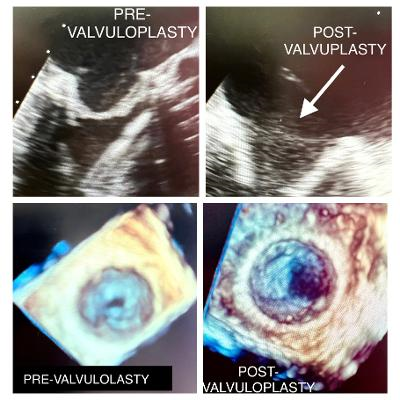

Via direct cannulation of the right superior pulmonary vein an 8-French 23-cm AVANTI+ sheath introducer (Cordis) was advanced into the left atrium (Figures 1, 2). A Confida wire (Medtronic) was then advanced into the left ventricle. A 22 x 5-mm Tyshak II balloon (B. Braun) was placed across the mitral valve (Figure 3) and adequately inflated resulting in immediate improvement in valve function (mean gradient of 3 mm Hg) and valve area 1.5 cm2 (Figure 4). The pulmonary vein was closed with a 4-0 Prolene polypropylene suture (Ethicon). Intraoperative echocardiography demonstrated significant leaflet motion improvement. Subsequently, the patient’s hemodynamics improved and ECMO was removed. The Impella was removed 9 days later.

Our technique involves the placement of a balloon catheter through the right superior pulmonary vein and inflation in the stenotic valve to break up adhesions to improve valve function. This approach is particularly attractive in high-risk patients who are deemed unsuitable for repeat open heart surgery due to comorbidities or advanced age. Our report is the first known case of direct pulmonary vein cannulation for mitral valvuploplasty.